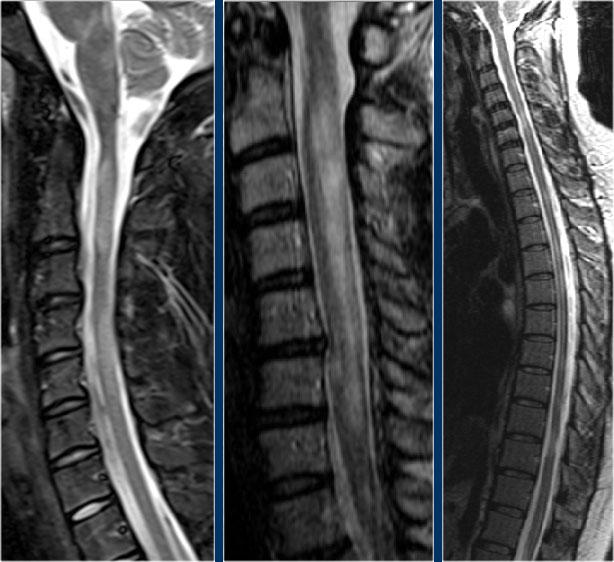

Hình ảnh mặt phẳng đứng dọc cho thấy một đoạn dài tăng tín hiệu trên chuỗi xung T2W.

Hình ảnh mặt phẳng ngang cho thấy phần lớn tủy sống bị tổn thương.

Đây là hình ảnh của bệnh nhân nam 31 tuổi với các triệu chứng đau đầu, rối loạn đi tiểu, bí tiểu, mức cảm giác tại C3.

Phân tích dịch não tủy (CSF) cho thấy 400/3 tế bào (không có dấu hiệu nhiễm trùng) và nồng độ protein tăng nhẹ.

Hình ảnh cho thấy bệnh lý tủy đoạn dài với tổn thương toàn bộ mặt cắt ngang.

Không có phù nề và không có ngấm thuốc tương phản từ.

Hình ảnh không điển hình cho xơ cứng rải rác (MS) hay u, do đó chúng tôi nghĩ đến ATM – viêm tủy cắt ngang cấp tính.

Đây là hình ảnh của một trường hợp TM điển hình.

Có tăng tín hiệu đa đoạn trên STIR và chuỗi xung T2W kèm theo phù nề nhẹ.

Phần lớn tủy sống trên đường kính ngang bị tổn thương.

Không có ngấm thuốc tương phản từ, đây thường là đặc điểm thường gặp trong TM.

Đôi khi có thể thấy ngấm thuốc dạng vá không đều.